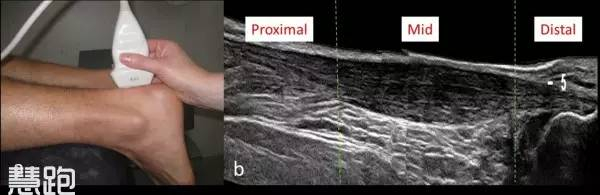

如果病史典型,且经过保守治疗康复有效,通常不需要辅助检查。X线对于诊断跟腱病没有帮助,超声和核磁共振有助于判断跟腱结构,常用于辅助检查;